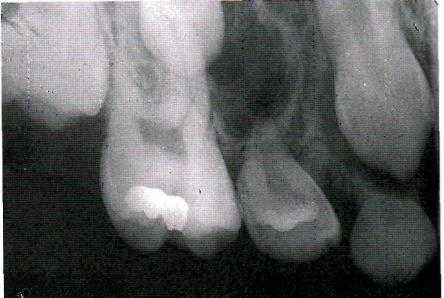

Рентгенологическая картина. Фиброма проявляется в виде гомогенного разряжения костной ткани округлой формы с относительно четкими границами. Патологический очаг окаймлен истонченным слоем кости без периостальной реакции. В центре очага могут быть участки петрификации.

Рентгенологическая картина. Определяется очаг деструкции костной ткани с нечеткими границами. В некоторых случаях может иметь вид мелких ячеистых образований, разделенных костными перегородками.

Рентгенологическая картина опухолевых поражений челюстных костей немногочисленна, это деструкция, деформация кости и периостальная реакция. Деструкция наблюдается в виде одиночного (фиброма, миксома, энхондрома, остеобластокластома, остеогенная саркома и др.) и множественных очагов (эозинофильная гранулёма, полиоссальная фиброзная дисплазия). Форма очагов деструкции может быть округлая, продолговатая, неправильная, очаги деструкции могут локализоваться в любом участке кости челюсти, располагаясь центрально или периферически.

Характер границ довольно типичен: так, остеома является прямым продолжением кортикального слоя и сливаясь с ним, располагается на поверхности кости. Очаг фиброзной дисплазии, располагаясь внутрикостно, имеет обычно четкую границу в виде склеротической каемки.